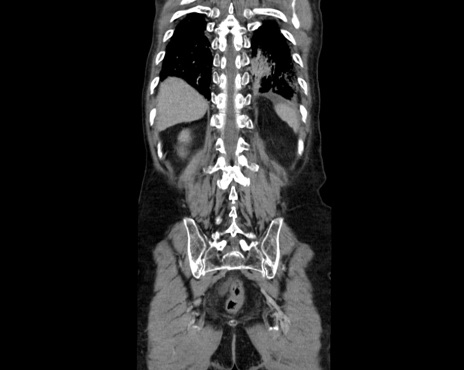

症例26(冠状断像)

【症例】80歳代男性

【主訴】嘔吐

【現病歴】昨晩2回嘔吐あり、今朝になっても嘔吐あり。来院。

【既往歴】胃潰瘍

【身体所見】意識清明、BT 37.6℃、BP 166/95mmHg、HR 100bpm、SpO2 97%、腹部:平坦・軟、腸蠕動音聴取良好、圧痛なし。

【データ】WBC 21900、CRP 1.4